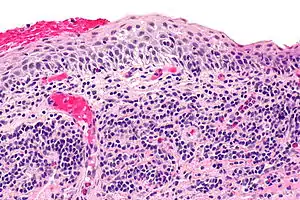

| Micrograph of plasmacytosis mucosae. H&E stain. | |